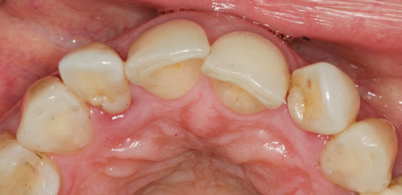

(6.) A 3-year, posttreatment photograph showing healthy tissue supporting the maxillary anterior teeth and correction of crowding.

Figure 6

Reevaluation of this case 3 years posttreatment (Figure 6) revealed normal probing depths, no bleeding on probing, a significant improvement in the angular bone loss on tooth No. 7 (Figure 7), and a stable periodontal condition. Prosthodontic treatment was delivered in a healthy environment and provided a stable occlusion and a satisfying overall appearance (Figure 8 through Figure 10). Preservation of this esthetic outcome was a motivating factor for the patient to maintain a high standard of oral care. For financial reasons and in consideration of her low smile line, the canines were not involved in the prosthodontic therapy.